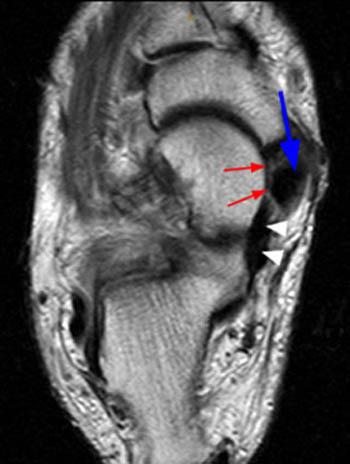

An mri of the knee of a healthy subject was performed in the 3 planes of space (coronal, axial, sagittal) commonly used in osteoarticular imaging, with two weightings most commonly used to explore the musculoskeletal pathology of the knee: Spring Ligament Tear - Radsource

Spring Ligament Tear - Radsource from radsource.us